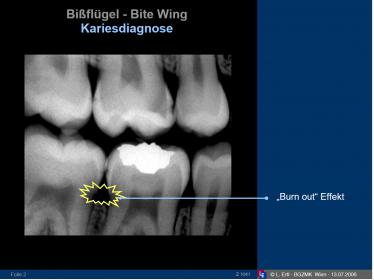

in diesem bereich kommen schmelz, dentin und wurzelzement zusammen, was in der röntgenprojektion häufig einen schatten wirft, man spricht von [B][URL=”http://www.meduniwien.ac.at/lukas.ertl/Download/Z-Hauptvo-03a-Karies.pdf”]burn-out effekt[/URL][/B].

wäre das karies, dann wäre dort deutlich mehr dynamik in dem jahr, die bilder sind nur unterschiedlich belichtet und so verzerrt sich die darstellung ein wenig und es wirkt ein wenig größer. unten ein bild zum thema burn-out effekt. ich würde nicht bohren und einfach nur in 6 monaten und in 12 monaten nochmals ein kleinbild machen …